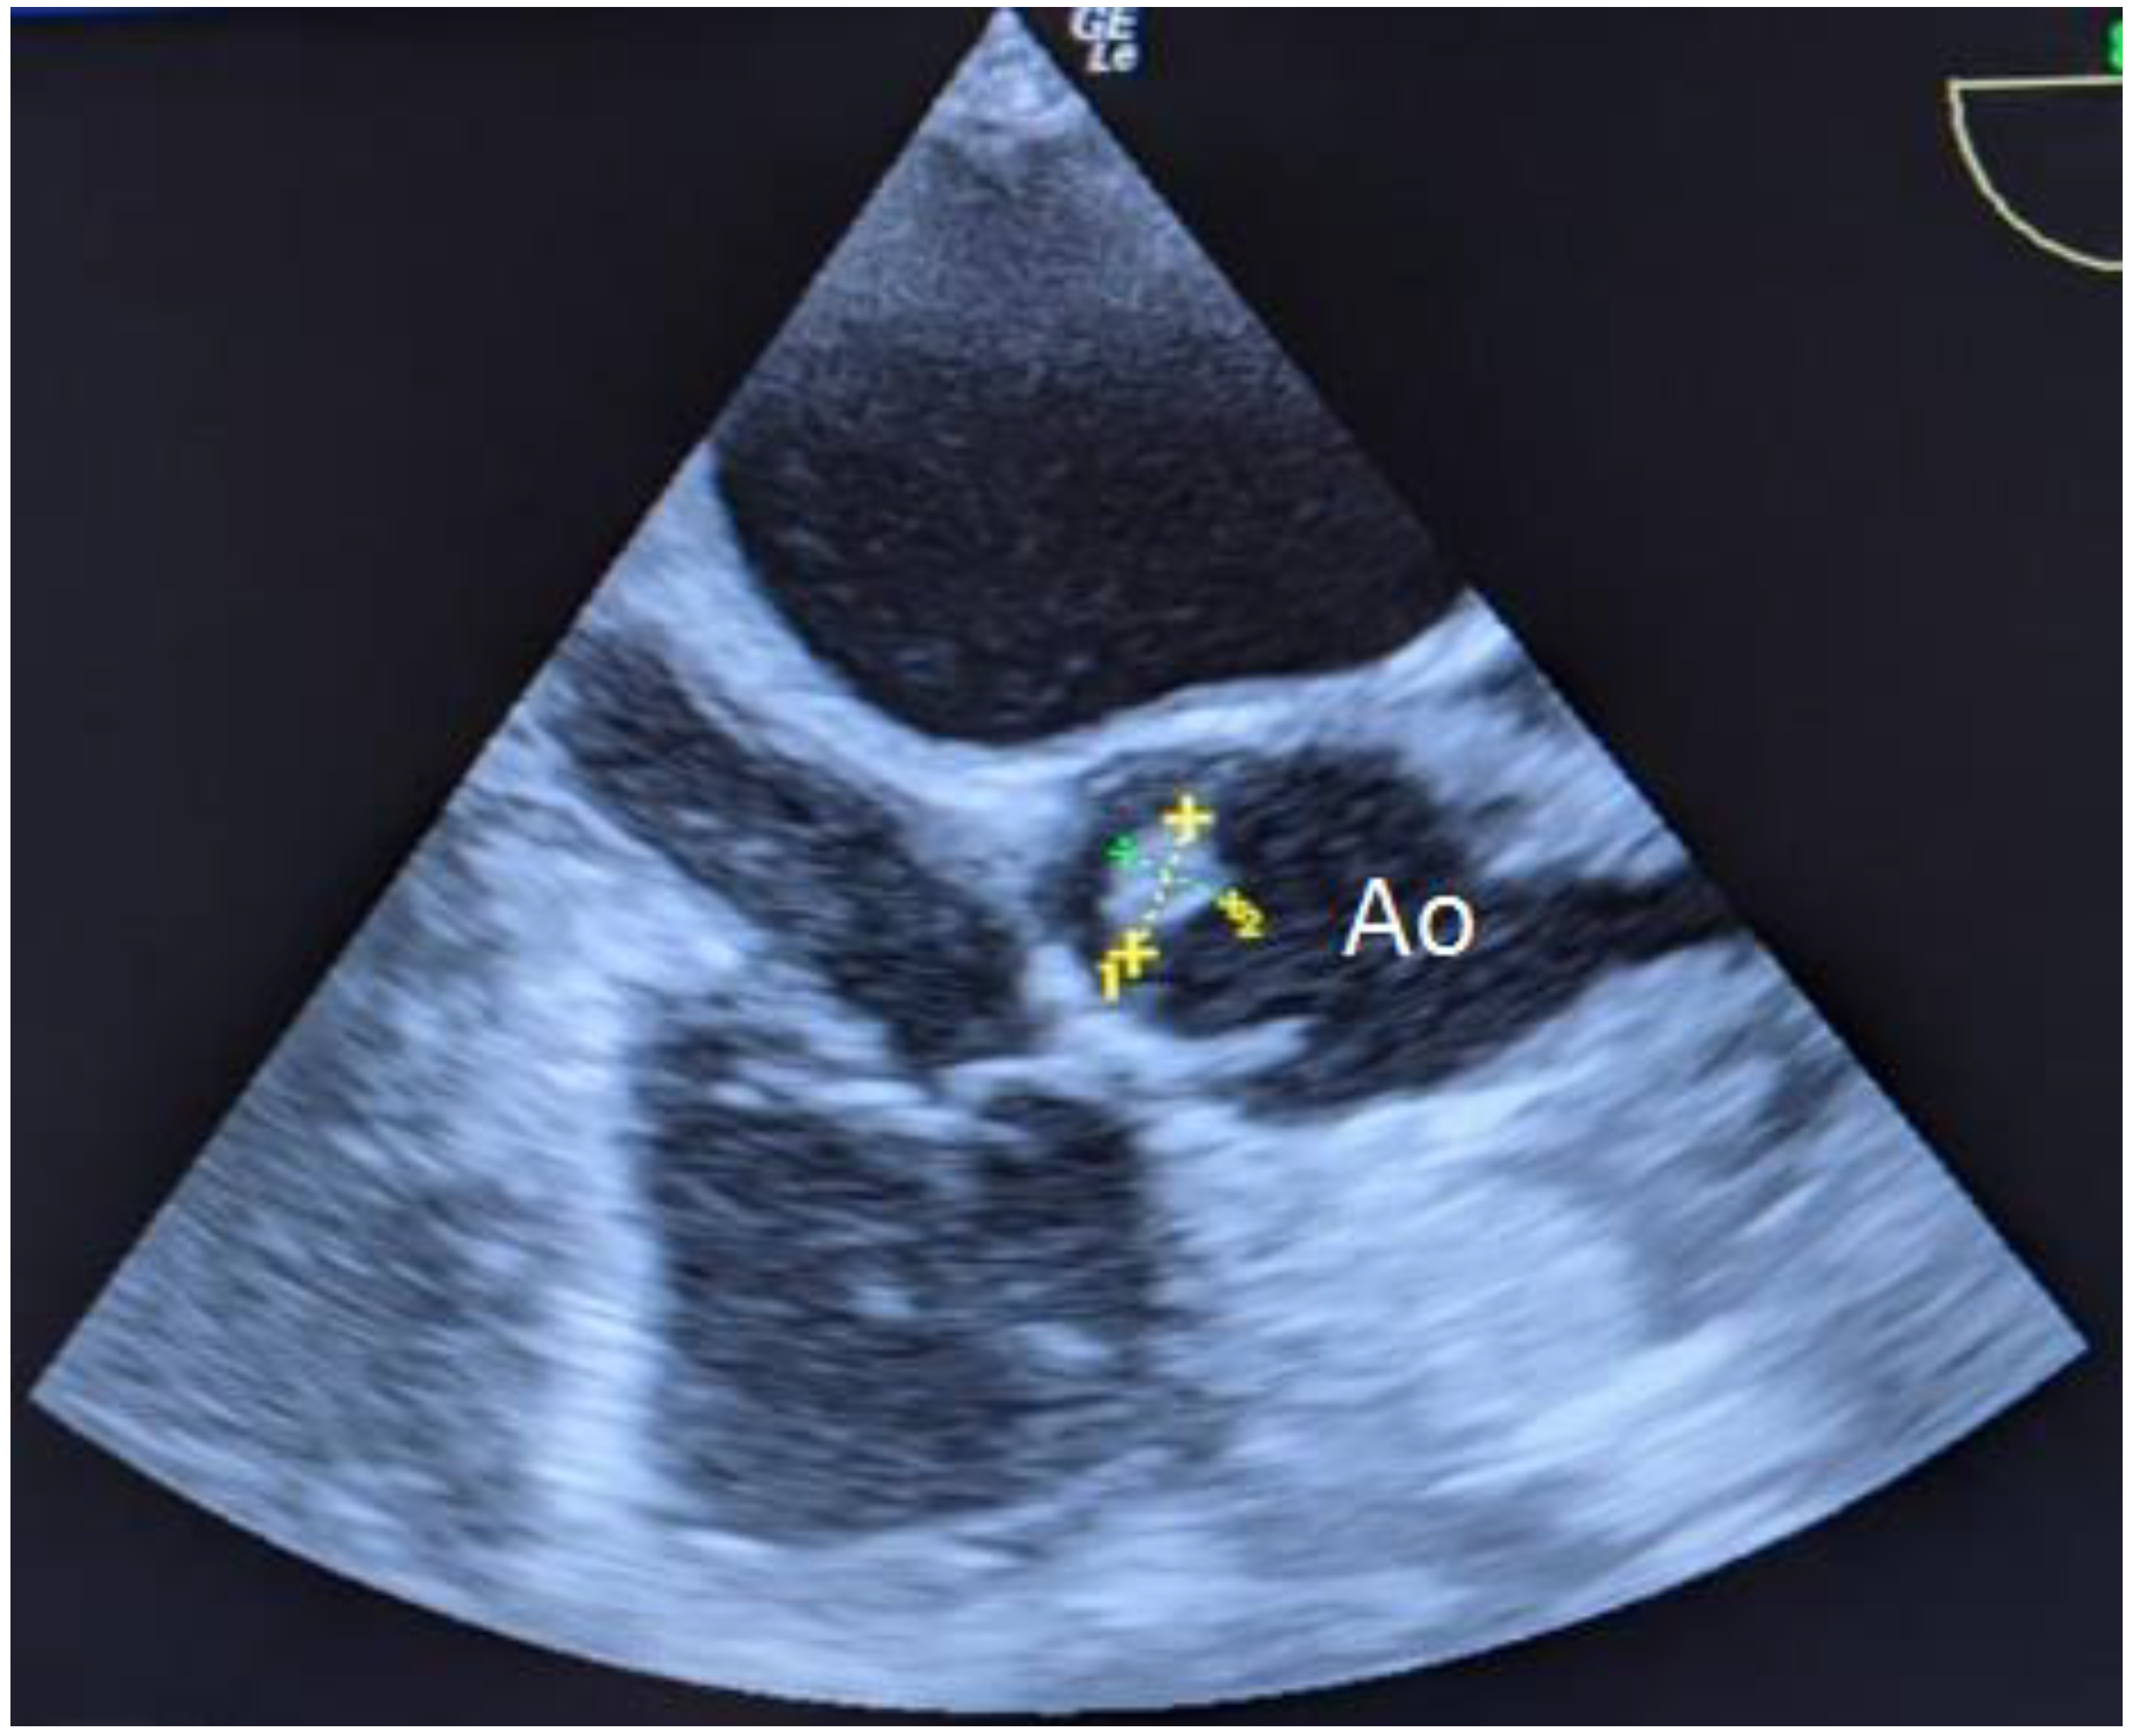

The TEE performed on the 3rd day revealed a hyperechogenic mobile structure of 10×9 mm in size located along the free edge of the noncoronary leaflet of the aortic valve (Figure 1).

Figure 1. Transesophageal echocardiography of the patient, 37 years old, on the 3rd day after admission. A hyperechogenic mobile structure located along the free edge of the noncoronary leaflet of the aortic valve is indicated.